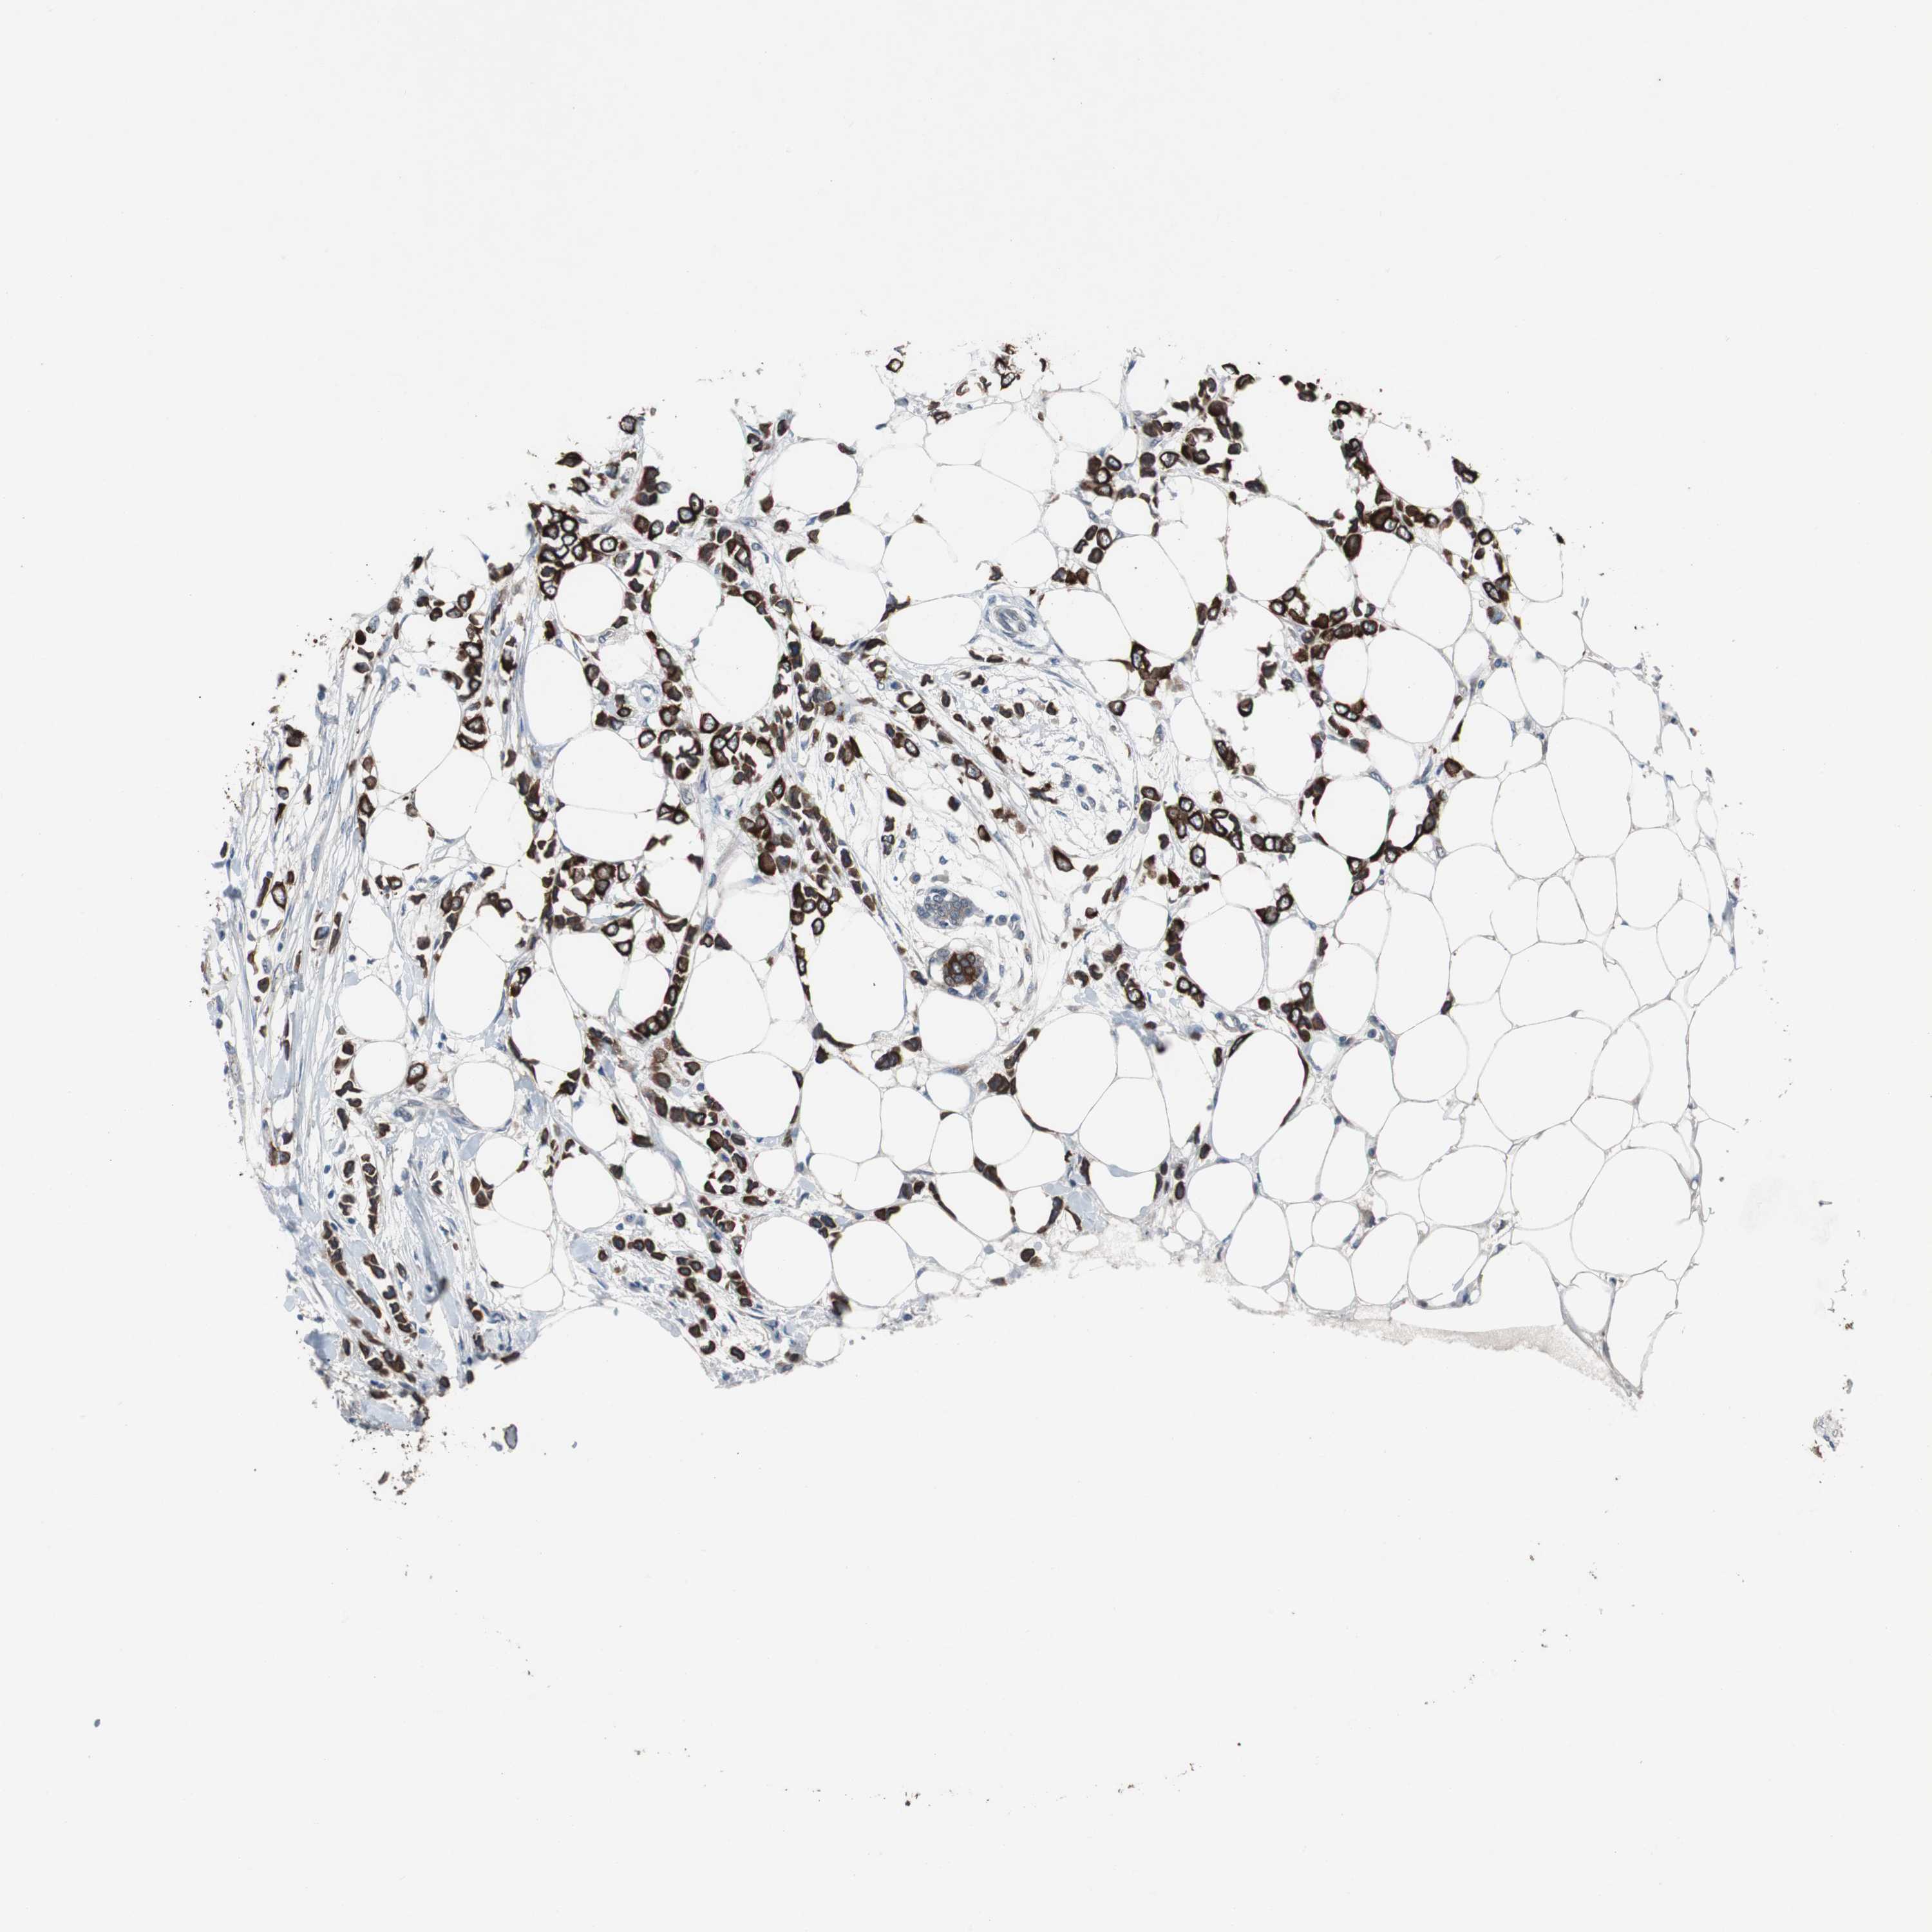

CANCER BREAST CANCER Show tissue menu

BRCA TCGA BRCA VALIDATION PROTEIN EXPRESSION